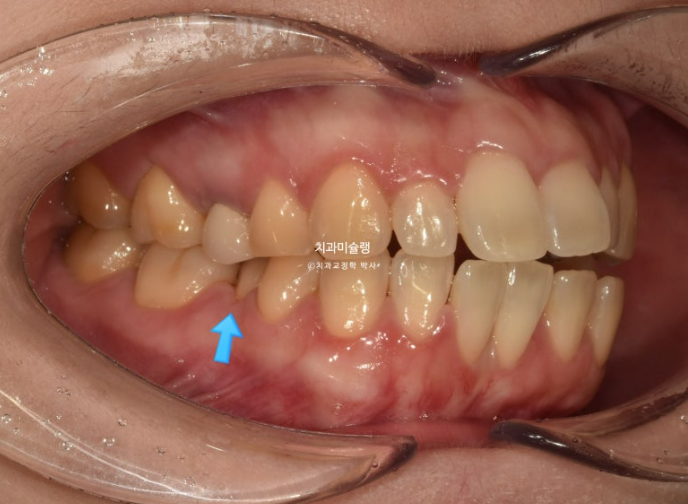

소구치에 윗니와 아랫니가 엇갈려 물리는 가위교합도 보입니다.

파란화살표는 가위교합 원인 치아입니다.

24.06